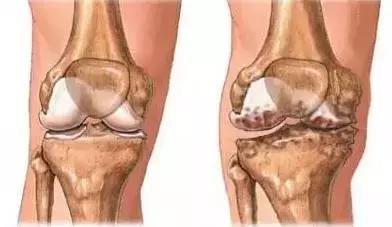

左侧:健康的膝关节,右侧:存在软骨磨损、骨刺、关节退行性变的膝关节